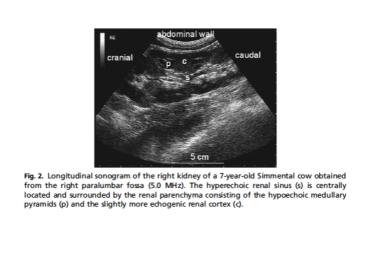

УЗИ моче-половой системы коров

Некоторое время назад разбиралась с УЗИ моче-половой системы коров (не совсем моя специализация). Надо признаться, это не рутинное исследование на фермах, потому даже в профилактических протоколах его нет. Более того, ...